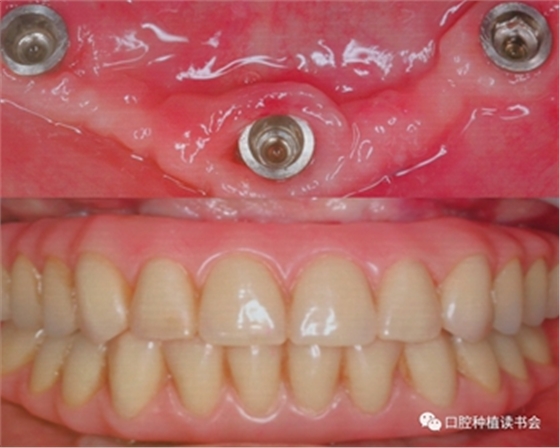

技師在模型上完成預(yù)成支架+樹(shù)脂義齒的制作,戴入口內(nèi)完成即刻負(fù)重,手術(shù)后兩個(gè)月觀察種植體軟硬組織整合良好(圖9、10)。

圖9 手術(shù)當(dāng)天制作的正式修復(fù)體

圖10 手術(shù)后兩個(gè)月觀察種植體軟硬組織整合良好,修復(fù)體使用良好

目前全世界有5個(gè)臨床中心,針對(duì)110名患者采用Trefoil下頜無(wú)牙頜種植修復(fù)理念,進(jìn)行5年的追蹤;從目前以發(fā)表的40名患者,共計(jì)120顆植體,1年的隨訪種植體成功率為97.6%。通過(guò)繼續(xù)的觀察,與現(xiàn)有的種植治療方式相比,Trefoil下頜無(wú)牙頜種植修復(fù)的臨床效果將進(jìn)一步得到確認(rèn)。